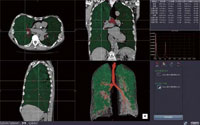

CT肺野・気管支測定

CTによる肺のCOPD(慢性閉塞性肺疾患)における気管支解析では,気管支の抽出が自動で行われ,1クリックによる気管支のパスの作成,ストレート CPR像が表示できる。さらに気管支の短径,長径,壁厚などの計測も簡単に行うことが可能で,肺のボリュームの測定も自動で行われる。また,肺の低吸収域(LAA%)の表示なども容易に行える。

CT肺野・気管支測定 CT肺野・気管支測定